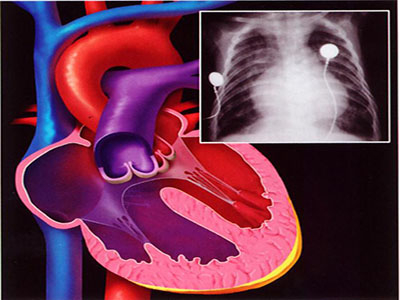

我們希望每個人都能了解心梗是怎麼回事,萬一自己或者家人遭遇這種情況,能最快的協助醫生做出決定。心梗,又叫心肌梗死,是給心髒供血的血管堵住了,心髒沒有血液的營養,就沒有辦法正常跳動,如果不及時糾正,生命就有危險。